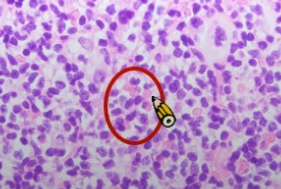

- starry sky pattern

- 星星:macrophages

- 夜空:核濃染的lymphoid cells其中的macrophage,其細胞質內含有apoptotic bodies

- 代表是high grade的lymphoma

- starry sky pattern